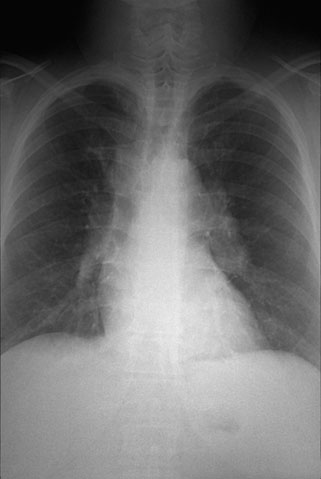

One cause for pulmonary intersitital fibrosis is sarcoidosis. In addition to increased interstitial markings, the chest radiograph may display prominent hilar lymphadenopathy (from non-caseating granulomatous inflammation) as shown here.